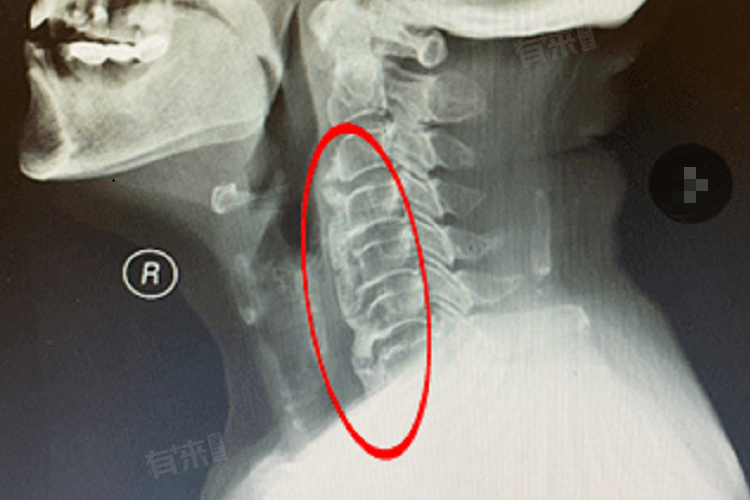

颈椎压迫食管的早期表现是一个复杂且多样化的过程,通常涉及多个方面的症状,比如吞咽困难与异物感、咽部与胸骨后不适、颈背部与上肢症状等。

3、颈背部与上肢症状:颈椎压迫食管不仅会影响食管本身,还可能引发颈背部和上肢的症状。患者可能会感到颈项疼痛、僵硬不适,以及肩部酸胀无力,由于神经根的受累,患者还可能出现上肢的疼痛、麻木和无力感,甚至可能出现手臂的放射性疼痛。